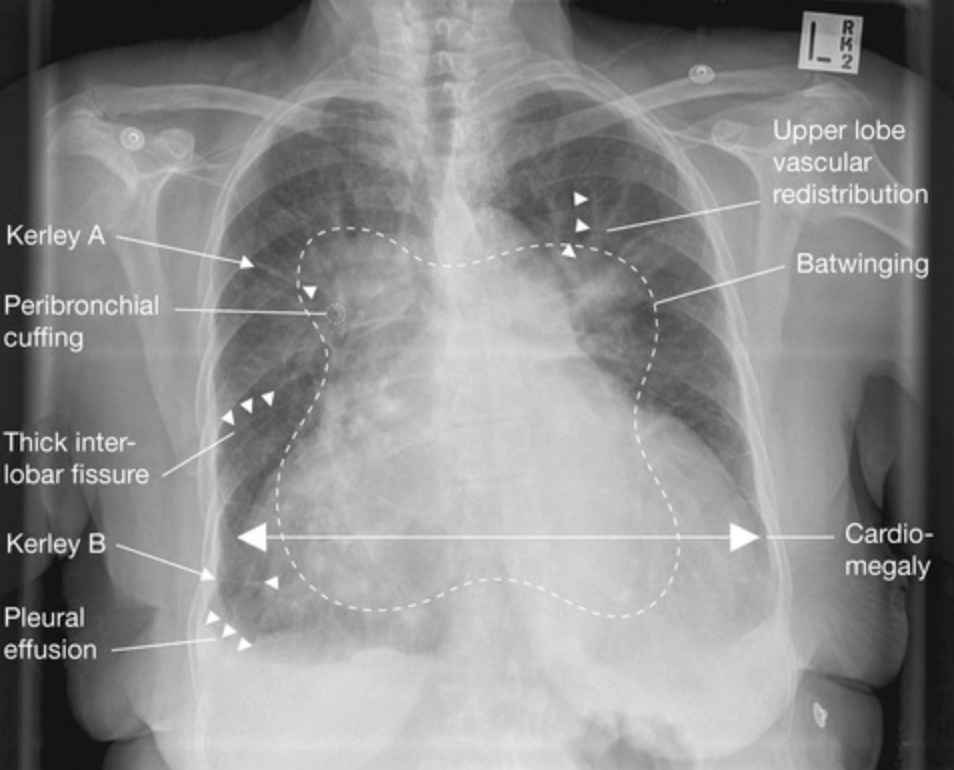

Chest-Xray

• Alveolar oedema (‘batwing’ appearance)

• Kerly B lines (1-2cm horizontal, peripheral engorged subpleural lymphatics) and septal lines

• Cardiomegaly

• Upper love diversion

• Pleural effusion

• Additionally to ABCDE features above; it may show a precipitating cause such as a pneumonia

• Progression

• Interstitial pulmonary oedema develops first

• Peribronchial cuffing

• Thickening of interlobar fissures

• Bat wing oedema is alveolar oedema in a non-gravity-dependent distribution; usually seen in hyper-acute heart failure (e.g. acute mitral incompetence due to papillary muscle rupture)